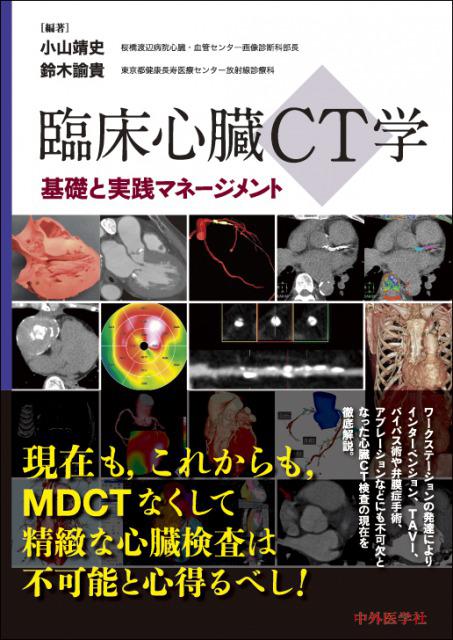

中外医学社 | 書籍詳細。臨床心臓CT学-基礎と実践マネージメント | 小山 靖史, 鈴木 諭。アプリケーション(心臓領域) | REVORAS。【N☆】令和6年(新米)コシヒカリ1等米10キロ。CT検査 | 戸畑共立病院。オプション検査 | 人間ドック健診センター | 大田区蒲田 牧田。。桜橋渡辺未来医療病院 MDCT検査予約。医学出版_循環器ナーシング16年6月号。CT検査 | 戸畑共立病院。心臓特化型画像診断センター「心臓画像クリニック(CVIC)飯田橋。朝倉書店『内科学』(第12版)デジタル付録。メジカルビュー社|診療放射線技師|心臓CT活用マニュアル。心臓Ⅰ:Step and shoot technique 岩城 卓(横浜栄共済病院。「臨床心臓CT学 基礎と実践マネージメント」小山 靖史定価: 22000円 (20000円+税)ぼぼ未使用でパラパラと見ただけで、状態はよいと思われます。書き込みも見返しましたがありませんでした(万が一あったら申し訳ございません)。表面に多少のスレやキズはあります。また天面に名前の印鑑がありマジックで消しています。あくまで写真のものをお渡しということでよろしくお願い致します。ご質問や価格交渉ありましたらメッセージくださいm(._.)m循環器内科、内科、カテ、カテーテル、CAG、PCI、FFRインターベンション、読影、放射線冠動脈、動脈硬化冠動脈疾患、虚血性心疾患、狭心症、心筋梗塞高血圧、糖尿病、脂質異常症、肥満